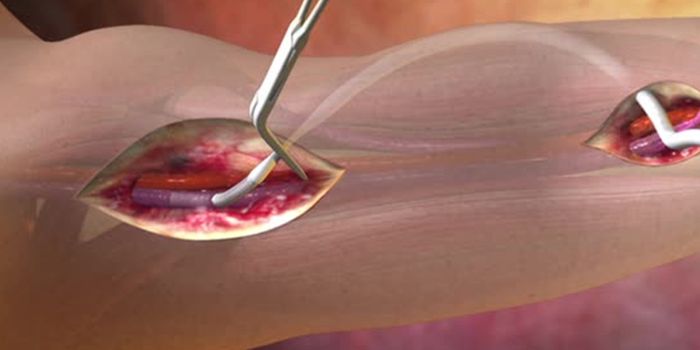

JAN 11, 2017Health & MedicineWith a constantly increasing amount of cardiovascular disease patients, doctors have more and more reasons to use vascul ...